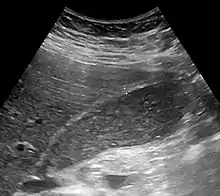

Abdominal ultrasonography showing biliary sludge and gallstones | |

Biliary sludge is typically diagnosed by CT scan or transabdominal ultrasonography.[1][2] Endoscopic ultrasonography is another more sensitive option. However, the gold standard is considered to be direct microscopy of aspirated gallbladder bile.[1][2] This method is much more sensitive, although it is less practical.[2]